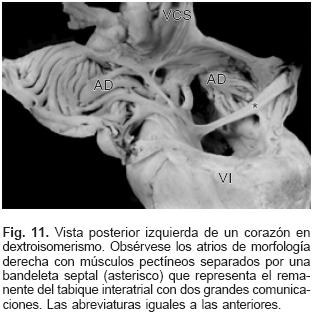

En el grupo mixto el trayecto de los colectores provenientes de cada pulmón dependió de los sitios de conexión anómala (Tabla II). Los setenta y tres corazones en situs solitus e inversas presentaron un defecto septal interatrial de tipo orificio oval (Figs. 2, 4, 7 y 9), mientras que en los treinta corazones con dextroisomerismo existió un atrio común y una bandeleta septal interatrial que separó dos grandes comunicaciones (Fig. 11). Todos los corazones presentaron dilatación de las cámaras derechas, del tronco y ramas de la arteria pulmonar así como hipertrofia del ventrículo derecho (Fig. 12). Respecto a las cámaras izquierdas el atrio fue pequeño e incompleto por carecer del SVP (Fig. 2), el ventrículo izquierdo y la válvula mitral tuvieron características normales. Las cardiopatías asociadas en los setenta y seis corazones con situs solitus e inversus se consignan en la Tabla III. Los treinta corazones con dextroisomerismo presentaron un patrón complejo de asociación de anomalías intracardíacas y vasculares (Tabla IV); en las Tablas V y VI se muestran respectivamente los tipos de conexión atrioventricular y ventriculoarterial en dextroisomerismo.

En el dextroisomerismo siempre está presente la CATVP; en esta condición ambos atrios tienen estructura morfológica derecha, y pueden ocurrir conexiones anómalas a venas cava superior, vertical y porta, mientras que está ausente la conexión a seno venoso coronario ya que esta cámara cardíaca no existe en este situs simétrico que presenta múltiples malformaciones cardiovasculares.